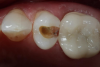

Fig 1. Example of image taken with transillumination technology. The dark area indicates caries.

Figure 1

Transillumination technology bathes the tooth in safe, near-infrared light, which makes the enamel appear transparent. This allows clinicians to see through the tooth, exposing its structure and allowing for highly accurate detection of the structure of any carious lesions. In porous tissue such as lesions, the light is trapped and absorbed. Images using transillumination technology are similar to X-rays, with lesions appearing as dark areas and healthy tooth structure as light areas (Figure 1). Therefore, this familiarity facilitates interpretation. In addition, NIR results are not affected by the presence of bacteria, and calibration is not required, as it is with other devices.2

Fig 6. Case 1. Initial opening of tooth reveals caries.

Figure 6